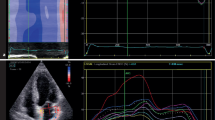

Echocardiograms were performed using routine clinical image acquisition (GE Vivid System E5, E7 and Vivid i, Chalfont, United Kingdom; Philips IE33 and CX50, Eindhoven, The Netherlands; Siemens Acuson Sequoia 512 and Aspen, Malvern PA, USA; Toshiba Artida, Otawara, Japan; all transducers 1–5 MHz; lab staffed by 25 sonographers, 10 physicians; Agfa HealthCare IMPAX Cardiovascular Suite, Greenville SC, USA), adhering to applicable guidelines (Lang et al. 2005). The size of the aortic root was recorded at three locations: (a) as the widest diameter at the level of the sinus of Valsalva, (b) at the sinotubular junction and (c) and as the largest diameter of the tubular portion of the ascending aorta as measured from inner edge to inner edge in the parasternal long-axis acoustic window (Fig. 1; Lang et al. 2005). It was decided pre-hoc to use ascending aortic diameter for the purpose of all data analyses in this study and aortic dilation was defined as an indexed diameter ≥2.1 cm/m2 as recommended elsewhere (Evangelista et al. 2010). LV outflow tract diameter was measured 0.5–1.0 cm below the aortic valve in a focused and zoomed-in parasternal long-axis view in mid-systole as the distance between basal septum and anterior mitral valve leaflet, and SV was obtained by multiplying LV outflow tract area (Lang et al. 2005) by the pulsed-wave Dopper velocity–time integral. LV end-diastolic volume (LVEDV) was obtained by dividing SV by LV ejection fraction (LVEF) and LV end-systolic volume (LVESV) was calculated by subsequently subtracting SV from LVEDV, a method validated in a porcine model against 3D echocardiography and post-mortem LV volumes (Hart et al. 2002). Arterial elastance (EA), which was introduced as an estimate of global afterload (Sunagawa et al. 1985) and subsequently validated against impedance measurements in the time domain (Kelly et al. 1992), was obtained by dividing LV end-systolic pressure [LVESP; estimated as 0.9 brachial systolic blood pressure (SBP)] by SV. End-systolic LV elastance (ELV) was used as a pre-load independent measure of LV contractility and calculated by dividing LVESP by LVESV (Sagawa et al. 1977), under the assumptions that end-systolic volume is linearly related to pressure and that V0 is negligible, both of which are reasonable under physiological loading conditions (Burkhoff et al. 2005; Kass and Kelly 1992). Arterial compliance (CA) was calculated by dividing SV by brachial pulse pressure, assuming a linear association between arterial volume and pressure (Chemla et al. 1998). Mean arterial pressure (MAP) was derived from brachial blood pressure as diastolic blood pressure (DBP) +PP/3. SVR was calculated as MAP divided by cardiac output. All chamber size data were indexed to body surface area (BSA) prior to any analyses (Asanoi et al. 1989; Najjar et al. 2004) and are shown in their indexed form throughout the article. Heart rate and brachial artery blood pressure were recorded immediately before echocardiography. The coefficient of variation for measurements of aortic root size, LVEF and SV, analyzed in 50 randomly selected studies as the standard deviation of differences divided by the mean, was 4.3, 7.6 and 8.6 %, respectively.

Favorable associations between aortic root dilation (x-axes) and both stroke volume and its principal determinants (y-axes). Panels show stroke volume (a), effective arterial elastance (LV afterload; b) end-systolic LV elastance (LV contractility; c) end-diastolic volume (LV preload; d) and heart rate (e). Patients with normal vs. dilated aortic root are shown in blue vs. red (color figure online)